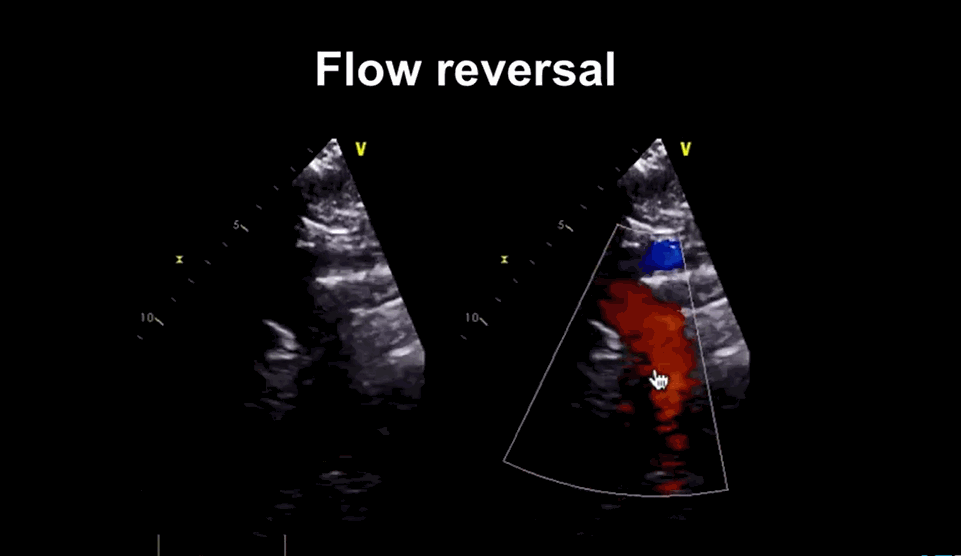

Now, we are able to document bizarre hemodynamics that happens the entire length of the vascular tree that is responsible for this murmur.(A related post 😦 In AR the run-off is central or periphery ?_)

Image courtesy: medmastery https://www.youtube.com/watch?v=eVhEXCO13ys

Phoncardiography with ECG correlation, help us to time the murmur exactly and also demonstrates reversal of flow in femoral artery by color flow doppler.